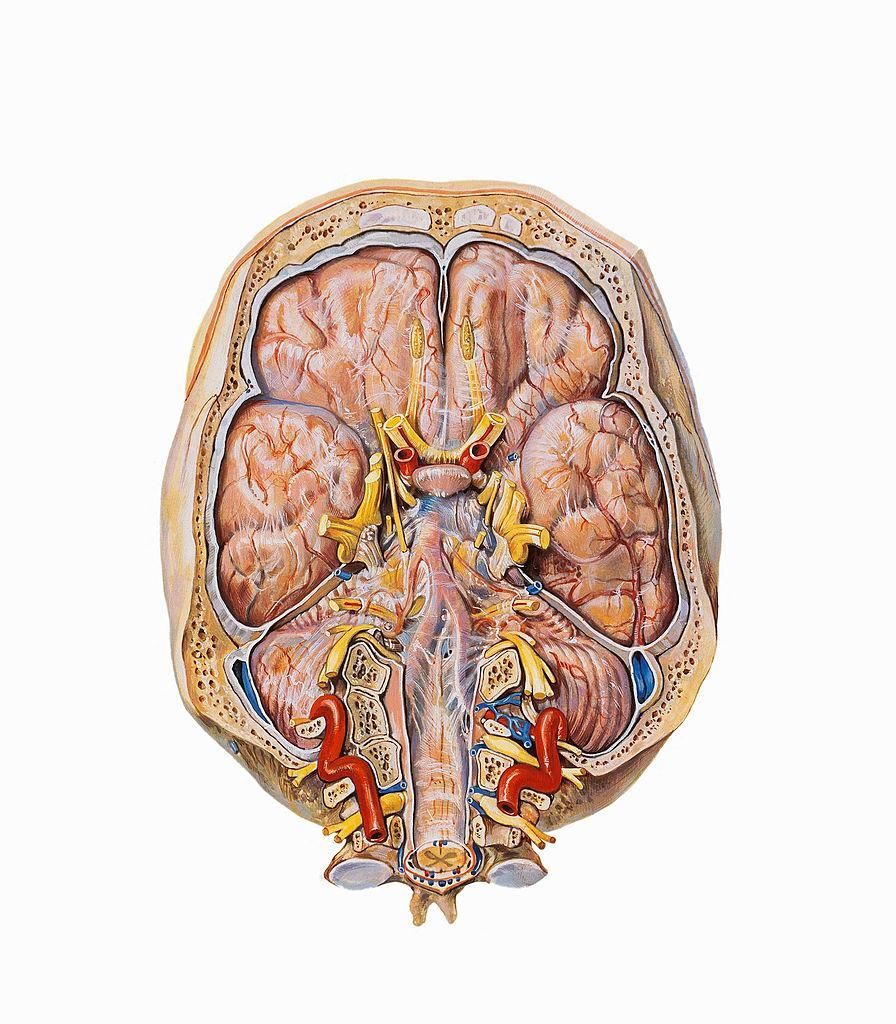

Il cervello è l’organo più complesso e meraviglioso del nostro corpo. Tuttavia, è una struttura misteriosa ed è avvolta da numerosi equivoci e bufale.